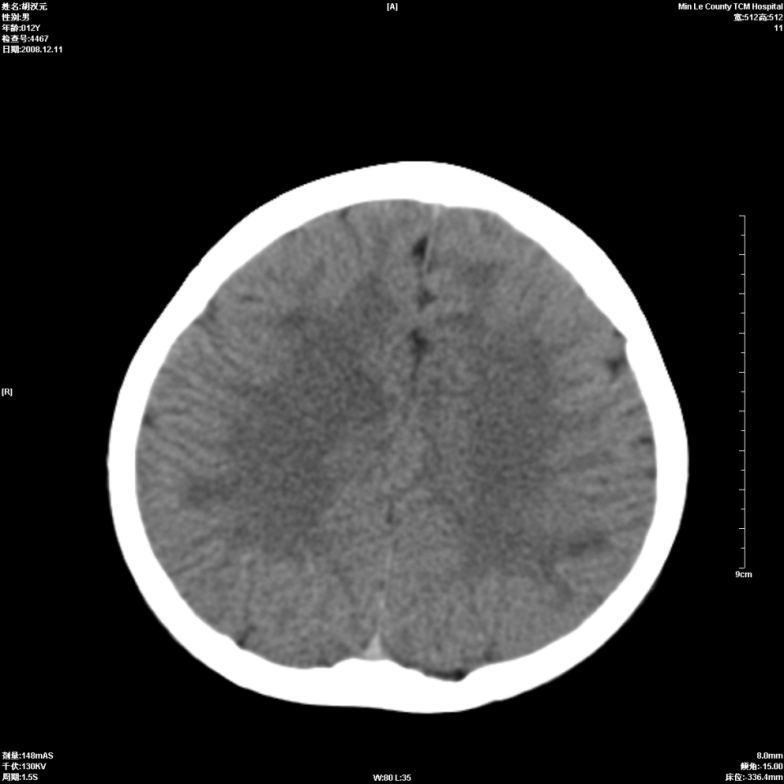

标题: PED1681:头疼发热约一周 [打印本页]

标题: PED1681:头疼发热约一周

颅脑未见确切异常。必要时进一步检查,如mri、脑脊液检查。

两侧顶部近灰质处白质密度降低,是否炎性改变

颅脑ct轴位平扫颅内未见明确异常;建议必要时复查或行进一步检查。

两侧顶部近灰质处白质密度降低,建议mri